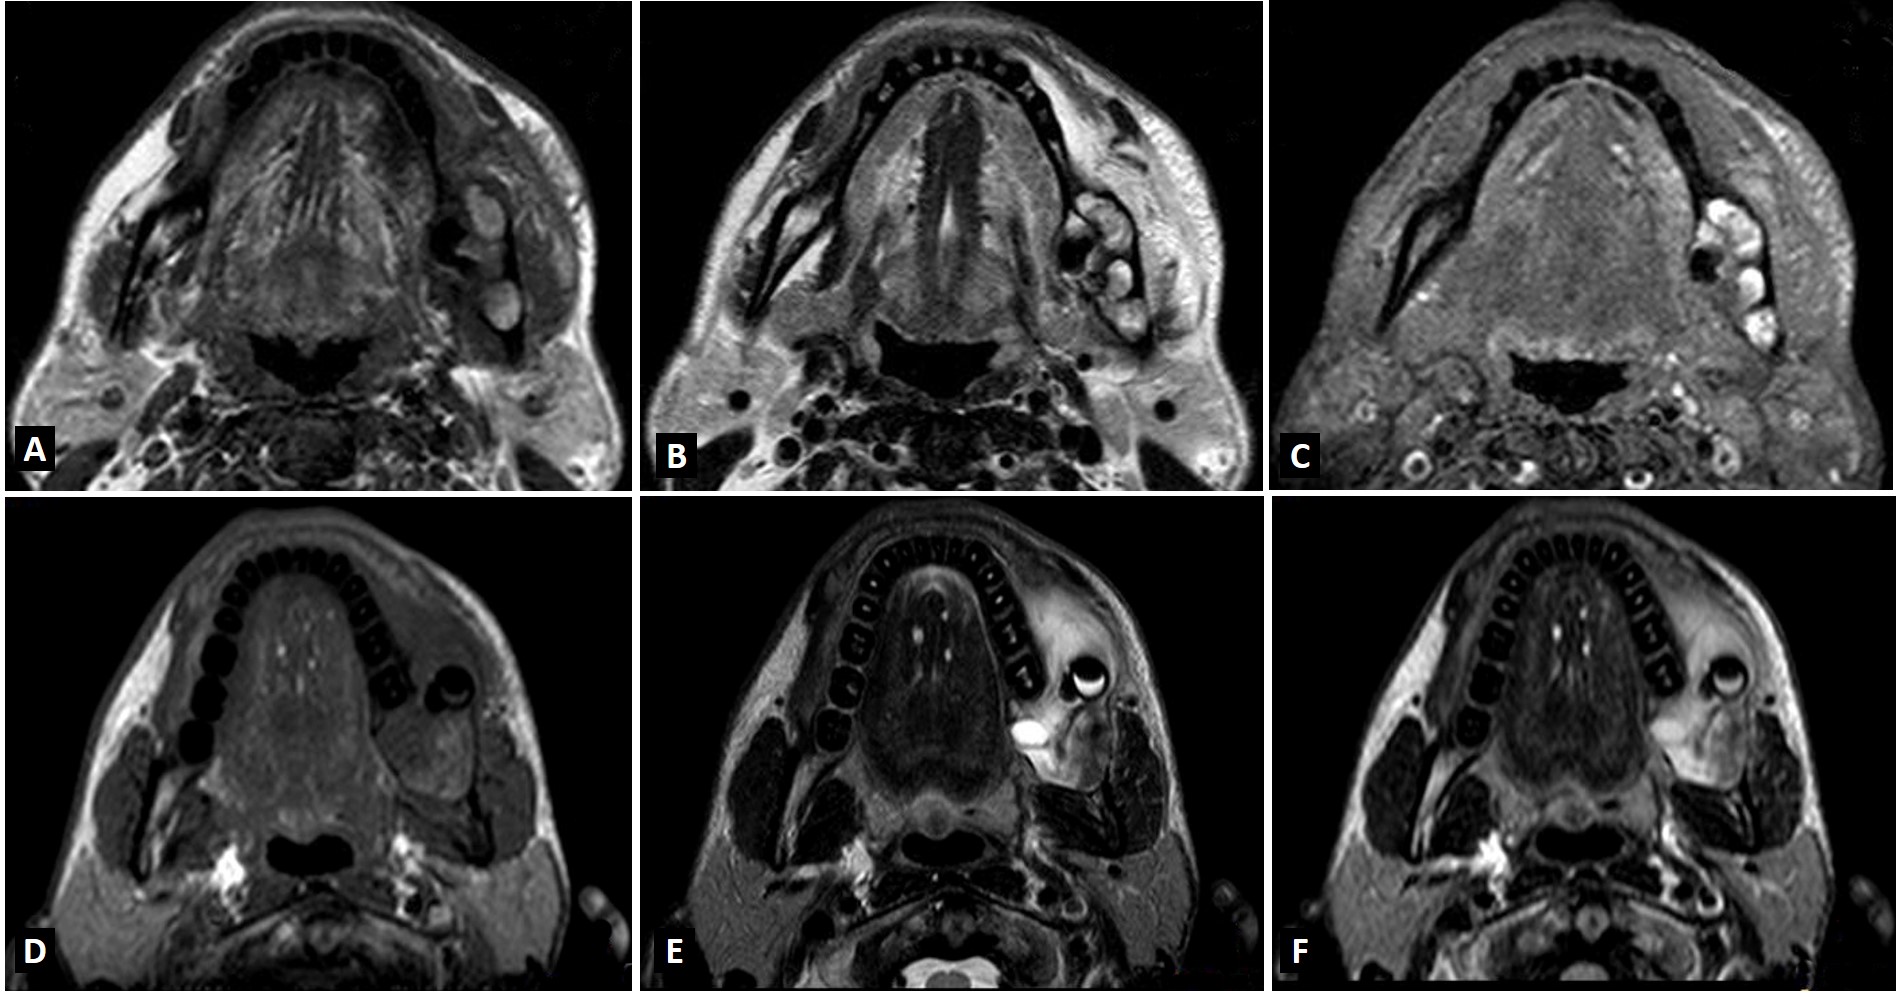

Ameloblastoma is an odontogenic tumor that shares clinical and imaging characteristics with other lesions of the jaws, such as odontogenic keratocyst, which makes the diagnosis difficult. However, in addition to radiographic and tomographic examinations, Magnetic Resonance Imaging (MRI) has been increasingly used, contributing with relevant additional information about the differentiation between solid and liquid components of the lesion. This case report was conducted to present two variations of ameloblastoma and discuss the radiographic, tomographic and MRI contribution in the differential diagnosis between ameloblastoma and odontogenic keratocyst.The signal intensity in T1-weighted MRI revealed internal fluid content in both cases, which was important in the differential diagnosis with other intraosseous lesions such as odontogenic keratocysts. This is probably due to the presence of keratin that increases the viscosity of the content and also for an intermediate signal intensity signal in T2-weighted MRI. Therefore, MRI revealed important internal characteristics of the reported lesions, which was very useful in the establishment of the differential diagnosis with other lesions.